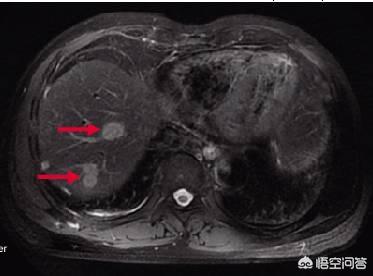

大腸癌の肝転移の発生率は高く、約50〜70%で、手術後あるいは以前から見つかることもある。原発巣が小さく、転移巣が大きいことも珍しくない。

腫瘍径が非常に小さく、一般に1~2mmで転移がある可能性があり、肝転移がなく腫瘍が非常に小さい場合は、TNM病期分類ではI期の患者である可能性が高く、簡単な手術で5年生存率が90%以上になり、完治する可能性が非常に高いが、肝転移が起こると状況が悪くなる。

大腸癌の肝転移は非常に多く、大腸癌患者はまず腹部CTと胸部CTを撮り、肝転移と肺転移の有無を確認しなければならない。実際、血行性転移によって、腸癌は局所転移のほかに、血流にのって癌細胞が排出され、血流に乗った後、血液循環にのって肝臓に入り、肝転移が現れます。肝転移が現れたら、実は進行期であり、肝転移が全く治療できないわけではありません。肝転移が乏転移性で、転移数が比較的少なく、転移部位が比較的良好であれば、大腸と肝臓の同時切除で根絶することができますが、転移が比較的大きい場合は、全身化学療法でコントロールする必要があります。